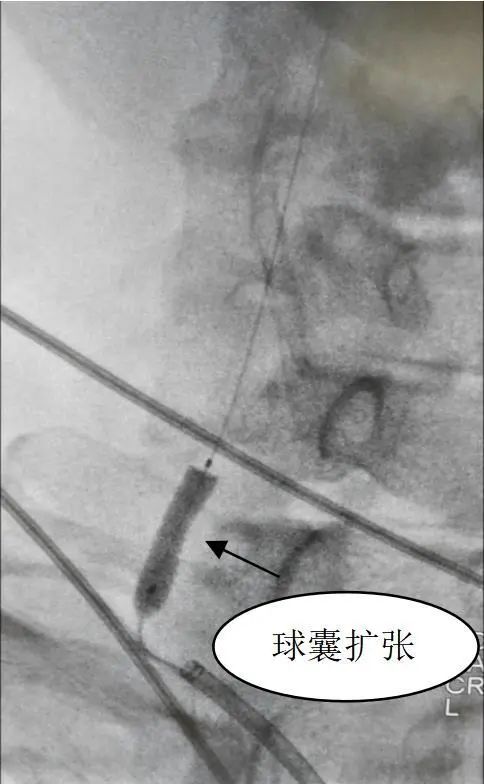

结合老张的情况,单峤带领的介入团队制定了手术方案,双侧颈内动脉闭塞无法挽回,计划实行右侧椎动脉狭窄球囊扩张及支架植入术,保障颅内代偿供血顺畅。

但因老张右侧椎动脉起始处极度狭窄及迂曲,常规方法微导丝难以通过,手术时,单峤果断换用多功能微导管导向,置入长交换微导丝顺利放入球囊扩张支架,再次造影见右侧椎动脉开口处狭窄明显改善,残余狭窄程度<10%,支架位置良好,手术顺利完成。